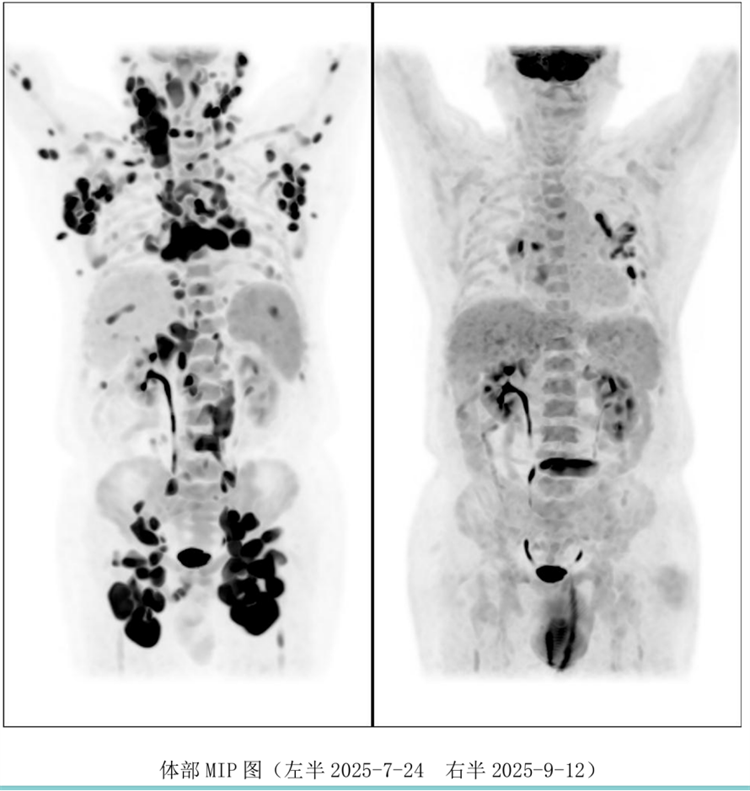

病例匯報環(huán)節(jié)由我院淋巴瘤科張薇醫(yī)生帶來了三例精彩紛呈的難治復(fù)發(fā)彌漫大B淋巴瘤CAR-T治療的病例。

病例過程跌宕起伏,從橋接治療到靶點(diǎn)的選擇,并發(fā)癥的處理都極具代表性。張醫(yī)生詳盡分享了患者在治療過程中的挑戰(zhàn)、決策依據(jù)以及CAR-T細(xì)胞治療后的驚人緩解與轉(zhuǎn)歸,充分展示了CAR-T技術(shù)為晚期患者帶來的突破性生存希望。